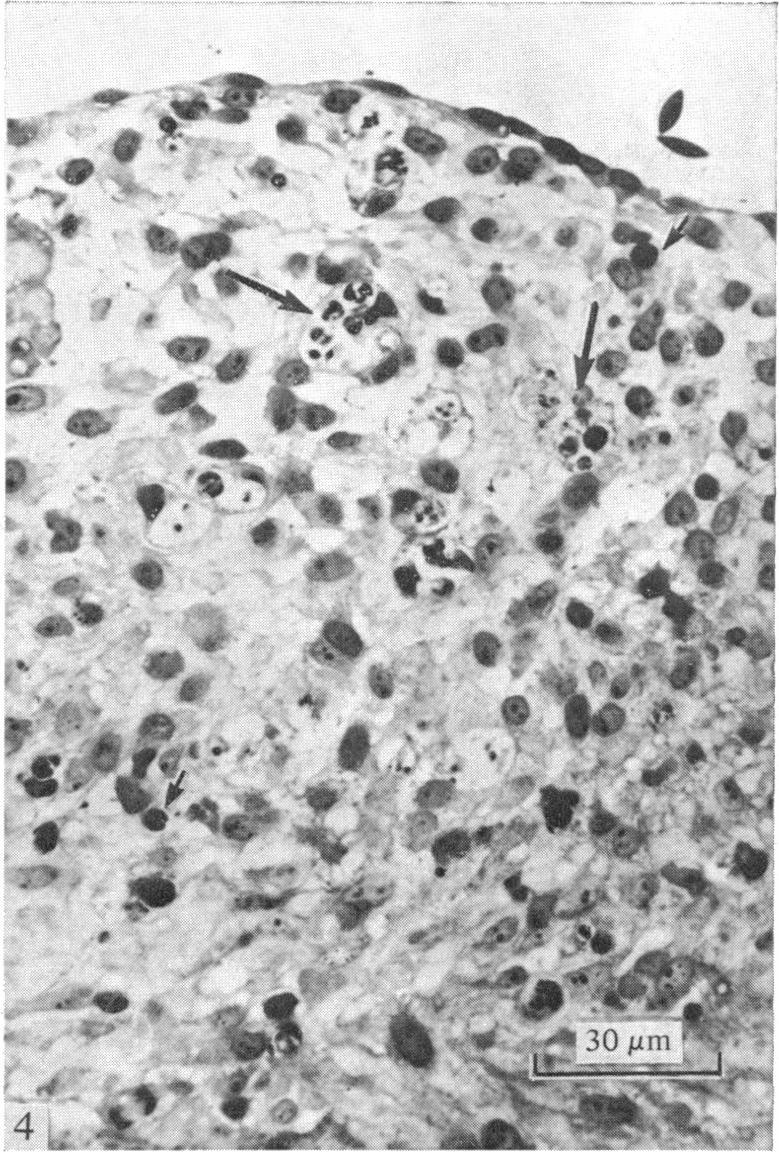

The presence of cell death in the walls of the truncus and conus of the developing chick heart was investigated by a variety of light and electron microscopic techniques. Necrotic areas were observed in the myocardial layer of the truncus and conus and within the mesenchymal cells of the truncoconal ridges and aortopulmonary septum. These necrotic zones appeared first at Stage 25-26 and reached their maximum extent at Stages 29-32 undergoing later progressive disappearance. The morphological changes of the degenerating cells detectable under both transmission and scanning electron microscopy are also reported. The possible role of cell death in the morphogenesis of the truncus and conus is discussed.